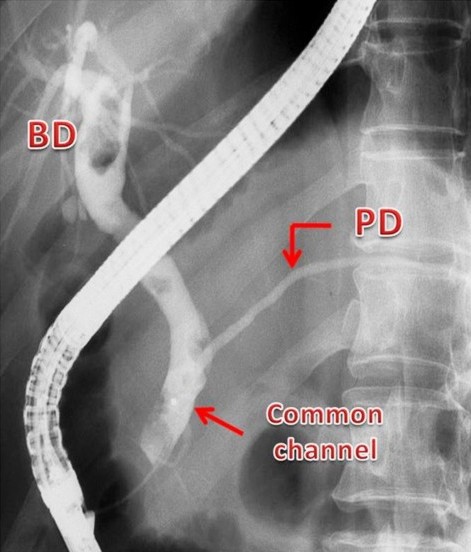

The reporting of the ERCPs was done in a stepwise fashion. The first step was to identify ERCPs in which both ducts were filled and pancreaticobiliary confluence was clearly identified in more than one image (inclusion criteria for study) (Figure 1). ERCPs in which only one duct (pancreatic or biliary) was filled or the confluence of the pancreatic and bile ducts was not clearly visualized were excluded from the study (Figure 1). Second, in those ERCPs included in the study, we then reported on whether the pancreatic and bile ducts opened into the duodenum separately or if the ducts were joined to each other and a common channel opened into the duodenum(Figure 2). Third, we measured the length of the common channel in the latter (Figure 3). To do so, we measured the actual length of the channel as it appeared on the images and corrected it with a magnification factor, as determined by the actual and imagined (as on images) width of the endoscope [15, 21]. If the corrected length of the united duct was less than 6 mm, it was reported as a short common channel. If the corrected length of the united duct was between 6 and 15 mm, it was reported as a long common channel. If the corrected length of the common channel was more than 15 mm, it was presumed that the ductal union had occurred outside the duodenal wall and such patients were reported as having anomalous pancreaticobiliary ductal union [20, 22]. For patients with anomalous pancreaticobiliary ductal union, we determined the pattern and angle of the ductal union. Anomalous pancreaticobiliary ductal union was reported as P-B type when the pancreatic duct appeared to join the bile duct and B-P type when the bile duct appeared to join the pancreatic duct. The angle of union was the actual angle at which the union occurred between two ducts [23].

Figure 3. Three ERCP images showing the definition of a short common channel (short CC: channel length 3 mm), a long common channel (long CC: channel length 12 mm) and anomalous pancreaticobiliary ductal union (anomalous pancreaticobiliary ductal union: channel length 4 cm). CC: common channel; PBDU: pancreaticobiliary ductal union |